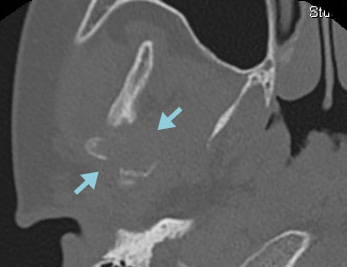

右下顎骨にLCHの骨再発をきたした。HU内服治療を開始後、溶骨部分の順調な修復が認められた。

CT 骨条件

ハイドロキシウレア開始時

2か月後

4か月後 * 患者さんから許可を得て掲載しています。